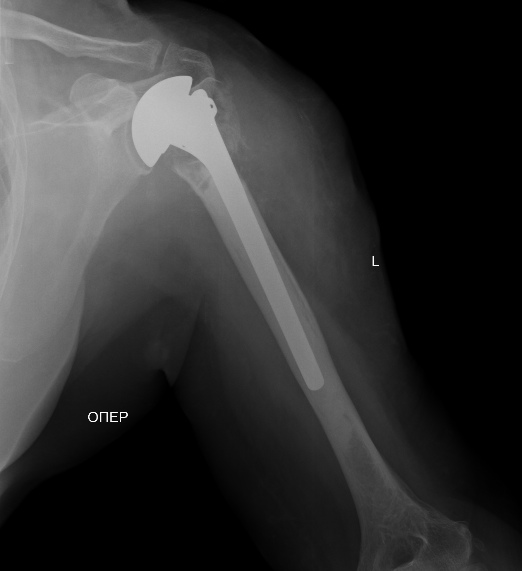

Анатолий Федорович, дорогой - чего там не видно на одном фасном снимкке,

без КТ даже? Перелом по анатомической шейке виден? Бугорки отломленные

видно? То, что суставная поверхность кнаружи-книзу смотрит, то есть

вывихнута, видно?

Остеосинтез можно сделать хоть спицами, но надо в любом случае открываться,

и не только вправить головку, но и фиксировать бугорки к плечу, то есть

сухожилия прошить хорошо. В приложении картинки с аналогичным переломом.

Имя     : 1.jpg

Тип     : image/jpeg

Размер  : 77502 байтов

Описание: отсутствует

Url     : http://weborto.net:8080/pipermail/ortho/attachments/20130830/3cf8e5fd/attachment-0002.jpg